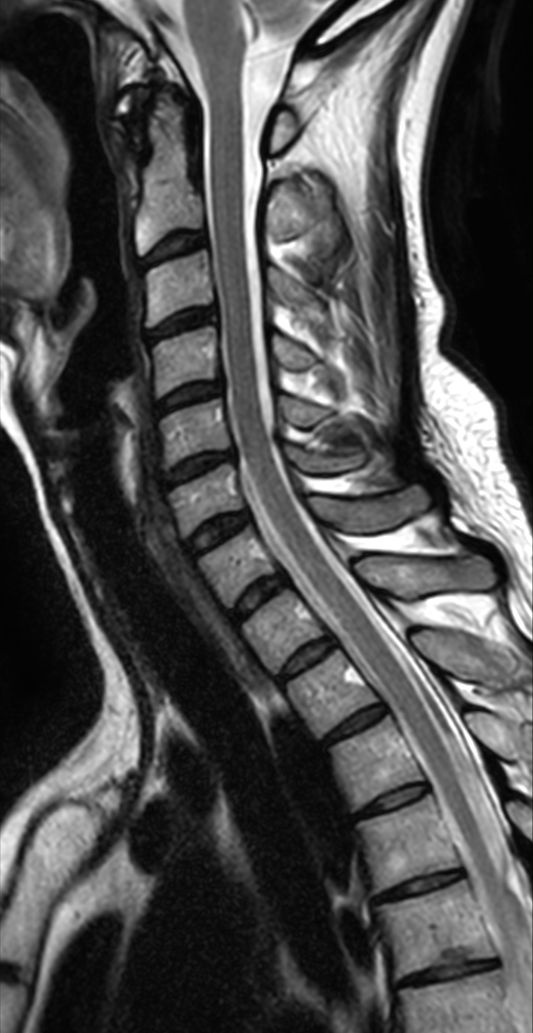

T2w TSE with ComforTone